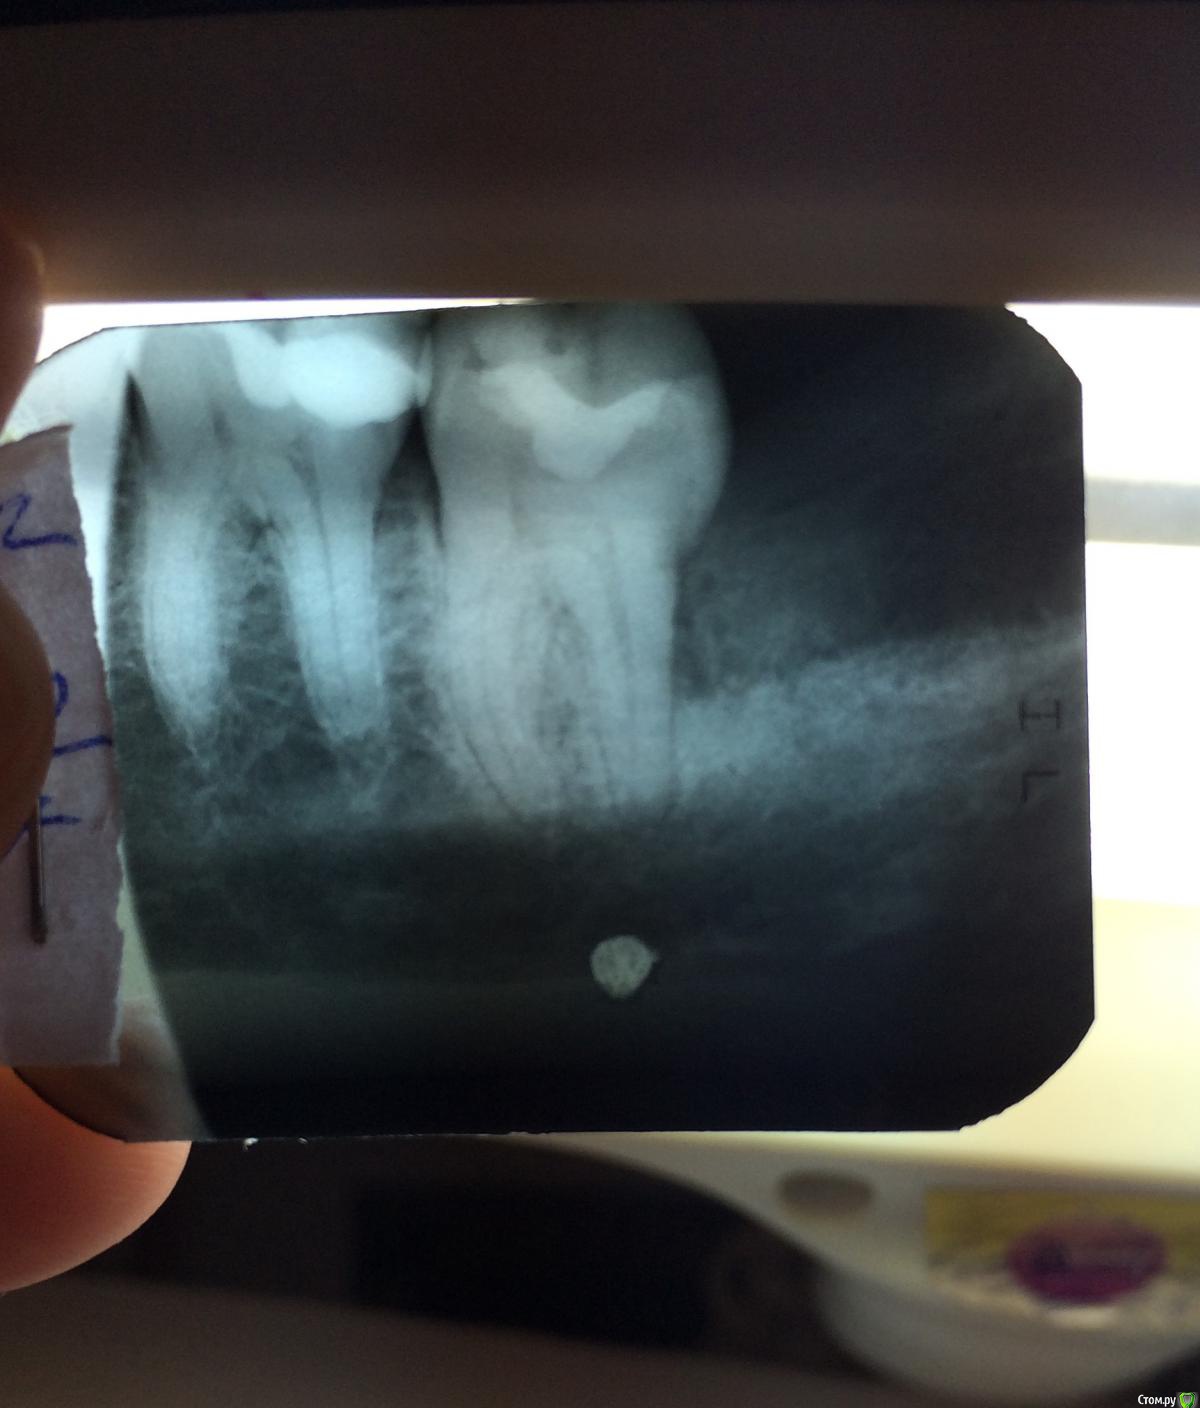

Irina2408 Опубликовано 4 марта, 2016 Поделиться Опубликовано 4 марта, 2016 Добрый день! Подскажите, пожалуйста, есть ли киста и периодонтит на 36 зубе? Один доктор говорит , что там киста и нужно удалять, другой говорит, что кисты нет, но есть периодонтит и потребуется долгое поэтапное лечение... И про 37 зуб расскажите, пож-та. Ссылка на комментарий

red_butler Опубликовано 4 марта, 2016 Поделиться Опубликовано 4 марта, 2016 Кисты нет, но лечить зубы нужно Ссылка на комментарий

red_butler Опубликовано 4 марта, 2016 Поделиться Опубликовано 4 марта, 2016 Спасибо. А вообще по этому снимку можно определить, какое конкретно потребуется лечение -депульпирование, лечение каналов? Или как говорится-,,вскрытие покажет,,?Одного снимка не достаточно для ответа, но как минимум смена пломб Ссылка на комментарий